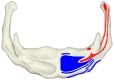

The mylohyoid muscle is flat and triangular, and is situated immediately superior to the anterior belly of the digastric muscle. It is classified as an anterior suprahyoid muscle. [ clarification needed ] Together, the paired mylohyoid muscles form a muscular floor ( diaphragm ) for the oral cavity (the mouth).[3] :212

The two mylohyoid muscles arise from the mandible at the mylohyoid line, which extends from the mandibular symphysis in front to the last molar tooth behind. The posterior fibers pass inferomedially and insert at anterior surface of the hyoid bone. The medial fibres of the two mylohyoid muscles unite in a midline raphe (where two muscles intermesh).[1] :987-8